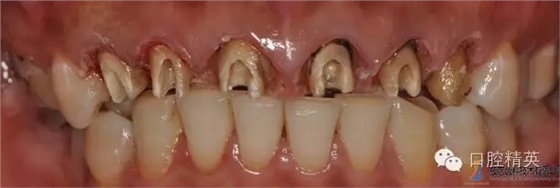

原金屬烤瓷冠

原金屬烤瓷牙咬頜觀